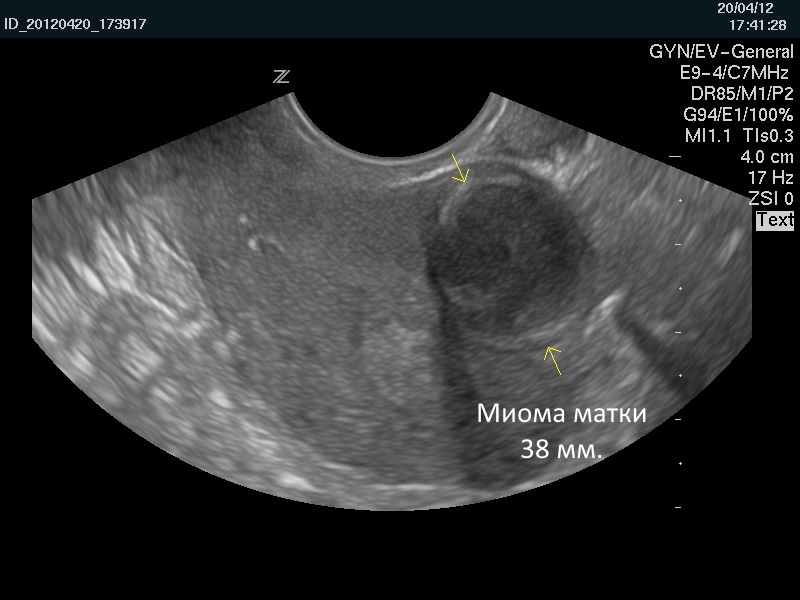

Размер миомы определяется с помощью УЗИ. Ее описывают в неделях и в сантиметрах. По мере роста новообразования матка увеличивается так же, как и во время беременности. То есть в случае увеличения матки на 10 неделе беременности женщине ставится диагноз «миома 10 недель». Размеры в неделях и см таковы:

Фото миом по размерам вы можете видеть ниже.

Ультразвуковое исследование (УЗИ) является одним из наиболее распространенных и доступных методов диагностики миомы матки. С помощью УЗИ можно получить информацию о размере, количестве и расположении миом. Исследование может проводиться как трансабдоминально (через переднюю стенку живота), так и трансвагинально (через влагалище), что позволяет получить более четкие изображения. УЗИ также помогает отслеживать динамику роста миомы на протяжении времени, что особенно важно для оценки рисков.